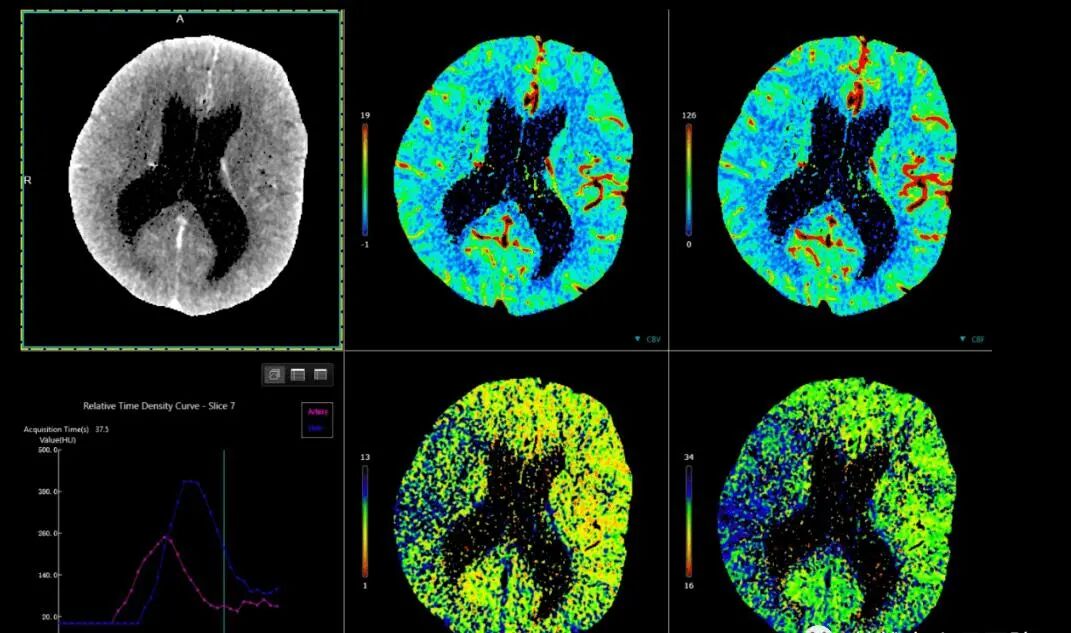

4、CT灌注成像:对评价急慢性脑缺血,肝、胰和骨骼的良恶性肿瘤的诊断具有巨大价值。

联影ct怎么样【医讯】勐腊县人民医院引进国产联影高端64排128层螺旋CT正式投入使用_https://www.jmylbn.com_新闻资讯_第8张